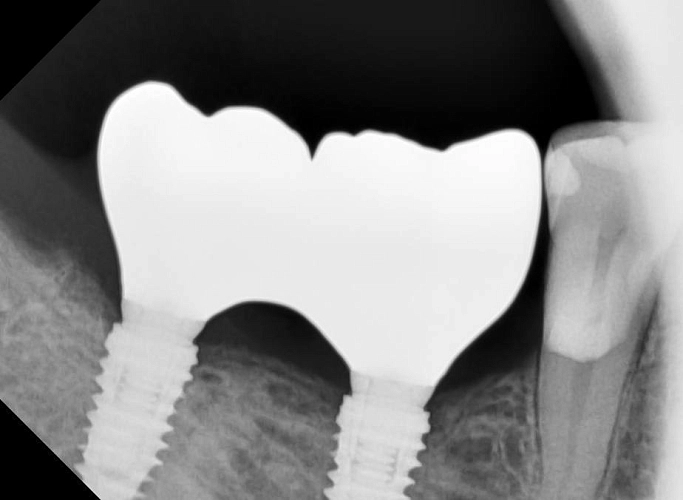

На фото представлен клинический случай.

Протезирование на имплантах с подготовкой костной ткани и десны в позиции зубов 47,47